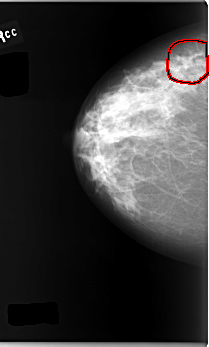

C_0095_1.RIGHT_CC

RIGHT_CC LINES 5888 PIXELS_PER_LINE 3544 BITS_PER_PIXEL 12 RESOLUTION 50 OVERLAY

FILE: C_0095_1.RIGHT_CC.OVERLAY

TOTAL_ABNORMALITIES 1

ABNORMALITY 1

LESION_TYPE MASS SHAPE IRREGULAR MARGINS SPICULATED

ASSESSMENT 4

SUBTLETY 3

PATHOLOGY MALIGNANT

TOTAL_OUTLINES 1

BOUNDARY